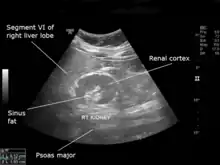

| An ultrasound scan of a hypoplastic right kidney in an adult male. | |

| Diagnostic method | Ultrasound |